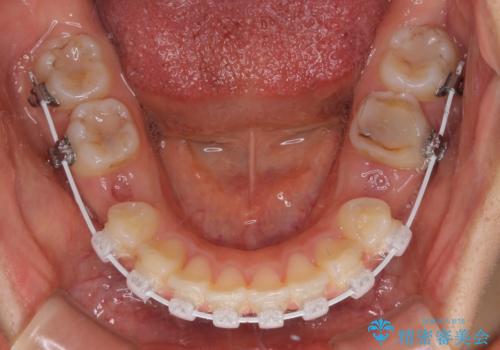

- 審美装置

- 2年2ヶ月

- 10-30回